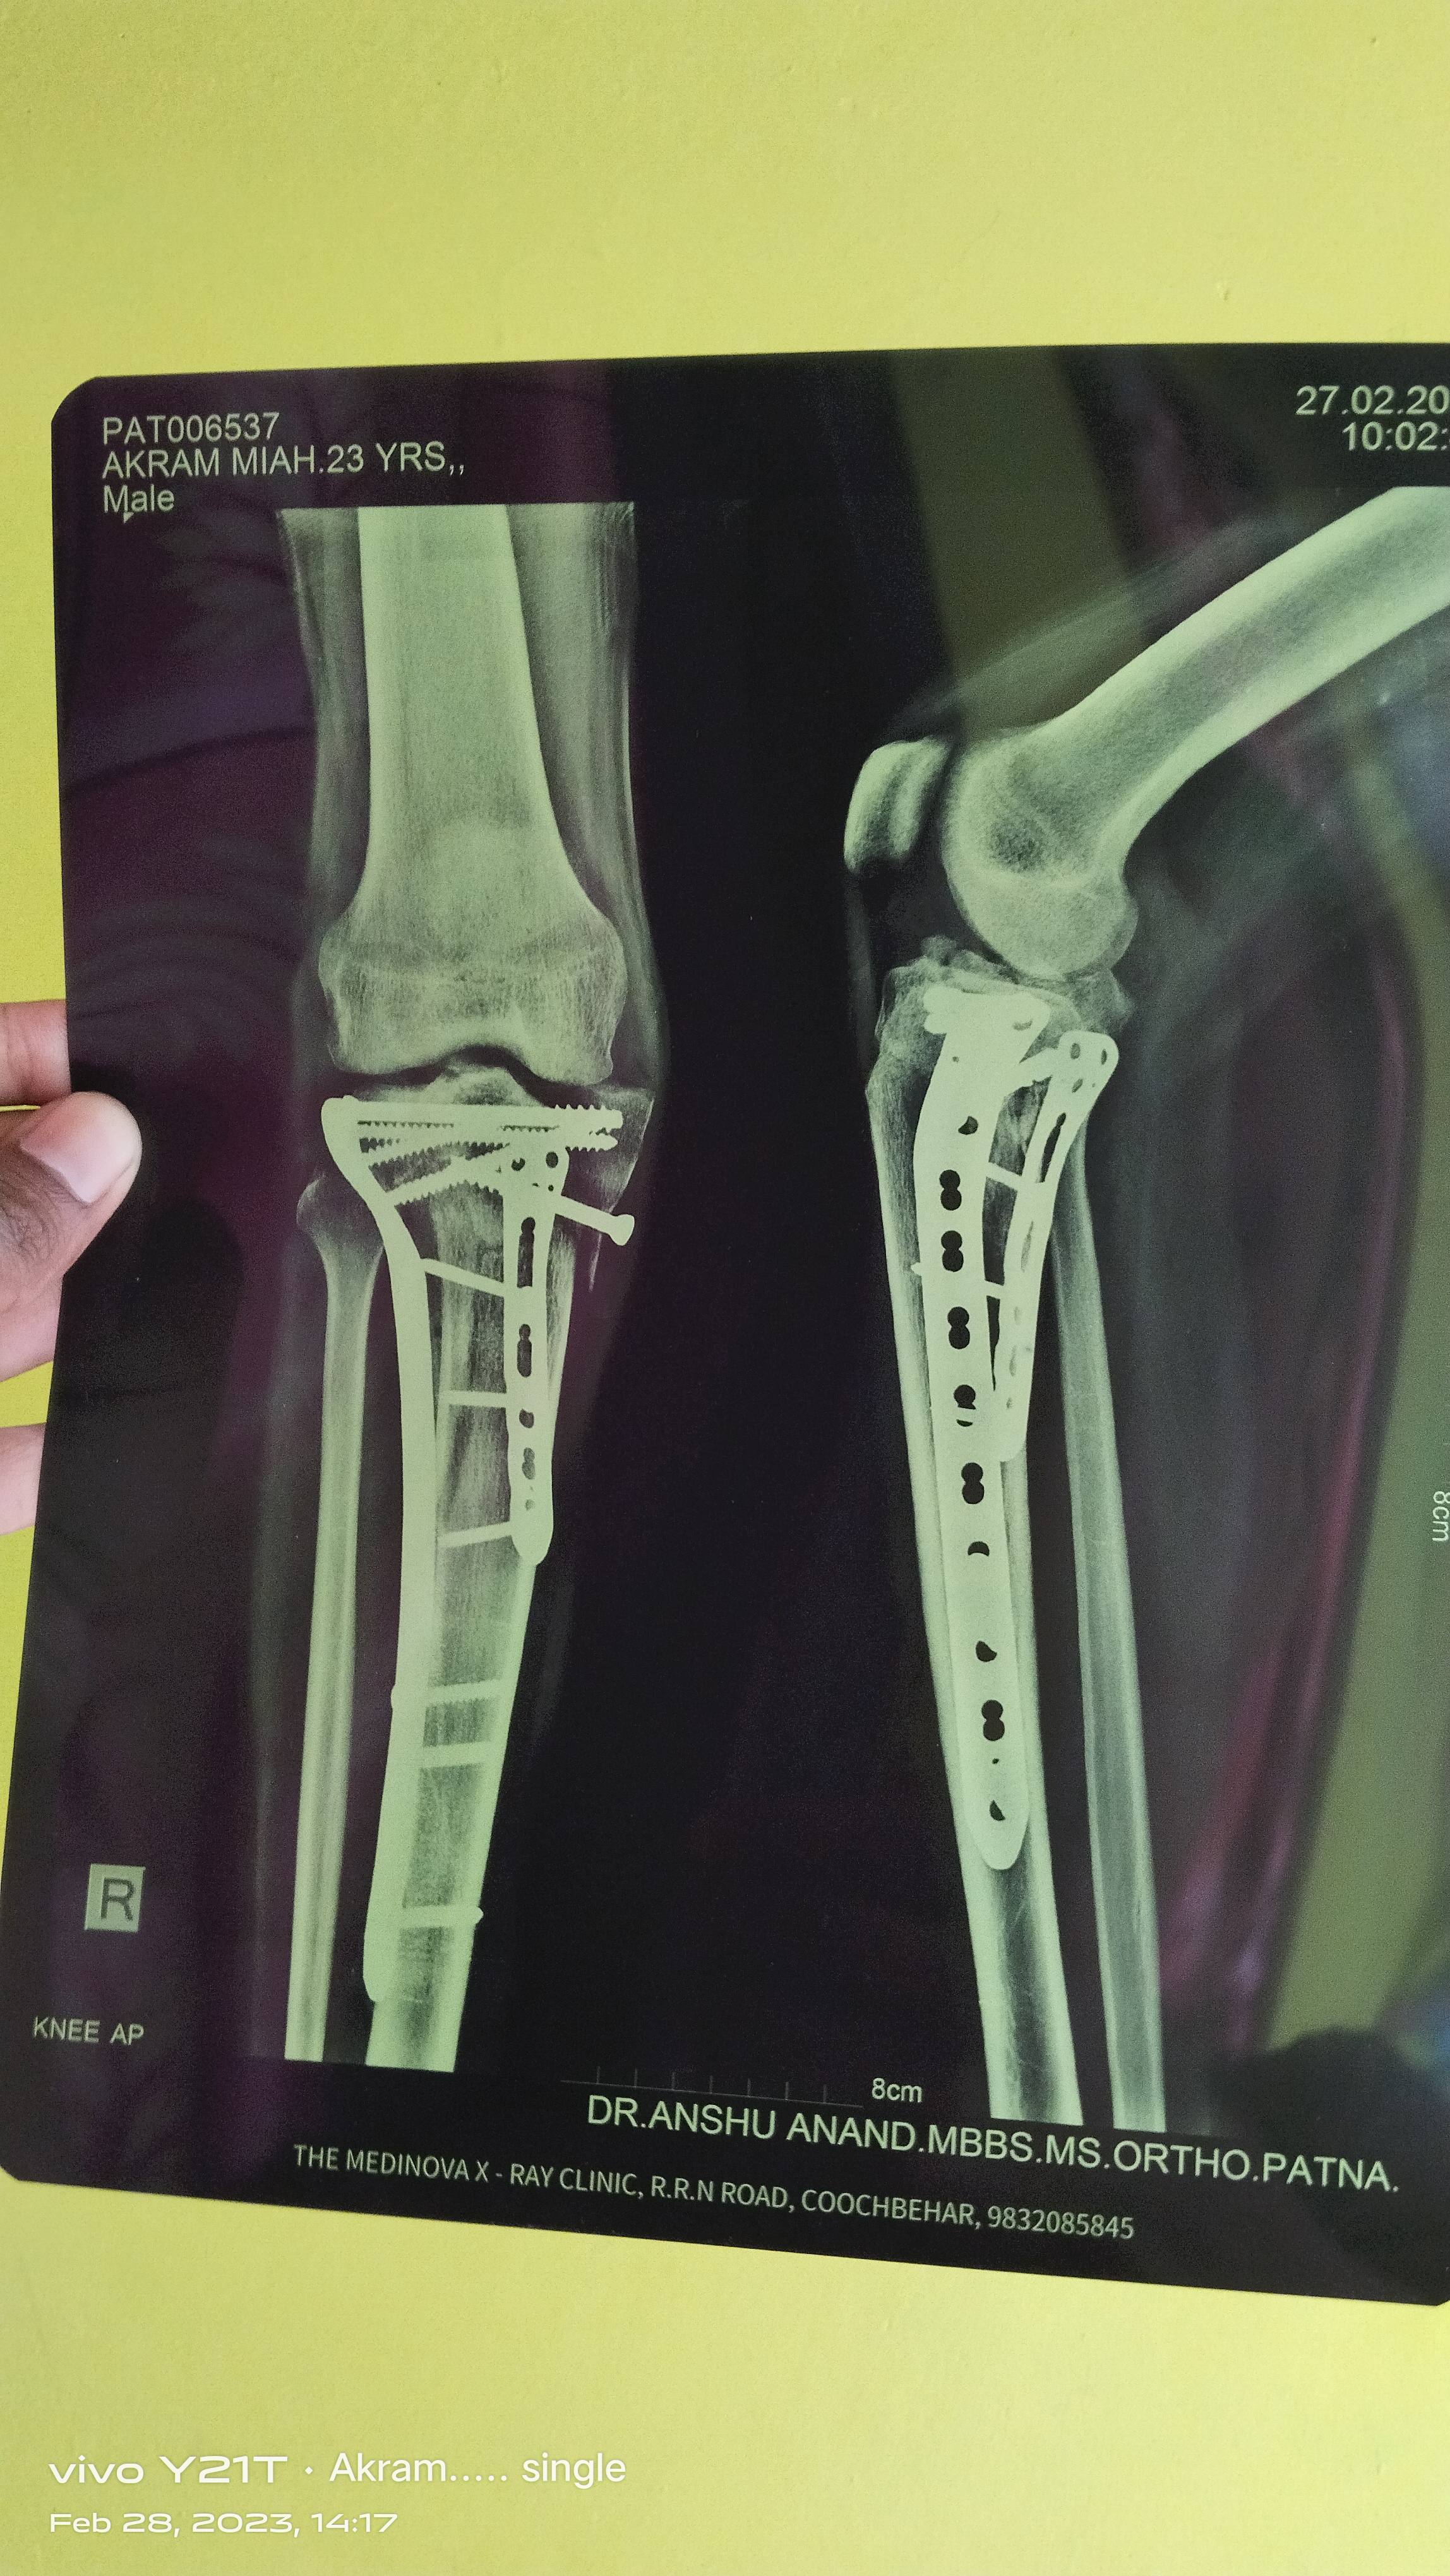

Akram mia